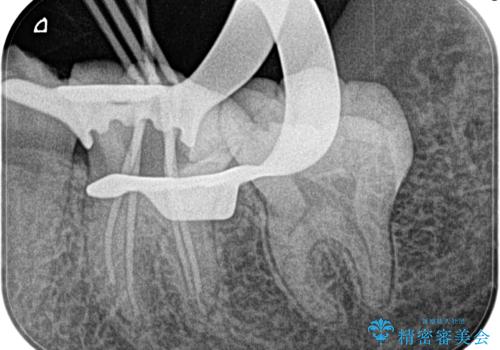

不可逆性歯髄炎の診断のもと根管治療を行なっております。

- 精密根管治療(イニシャルケース,大臼歯):122,000円、ファイバーコア:22,000円費用は治療当時の料金となります

根管治療は1回ごとにまとまった時間で治療を行うことにより2~3回の治療で完了します。

治癒不良の場合は外科的歯内療法の適応となります。

根管治療した歯は、クラウン修復が必要です。